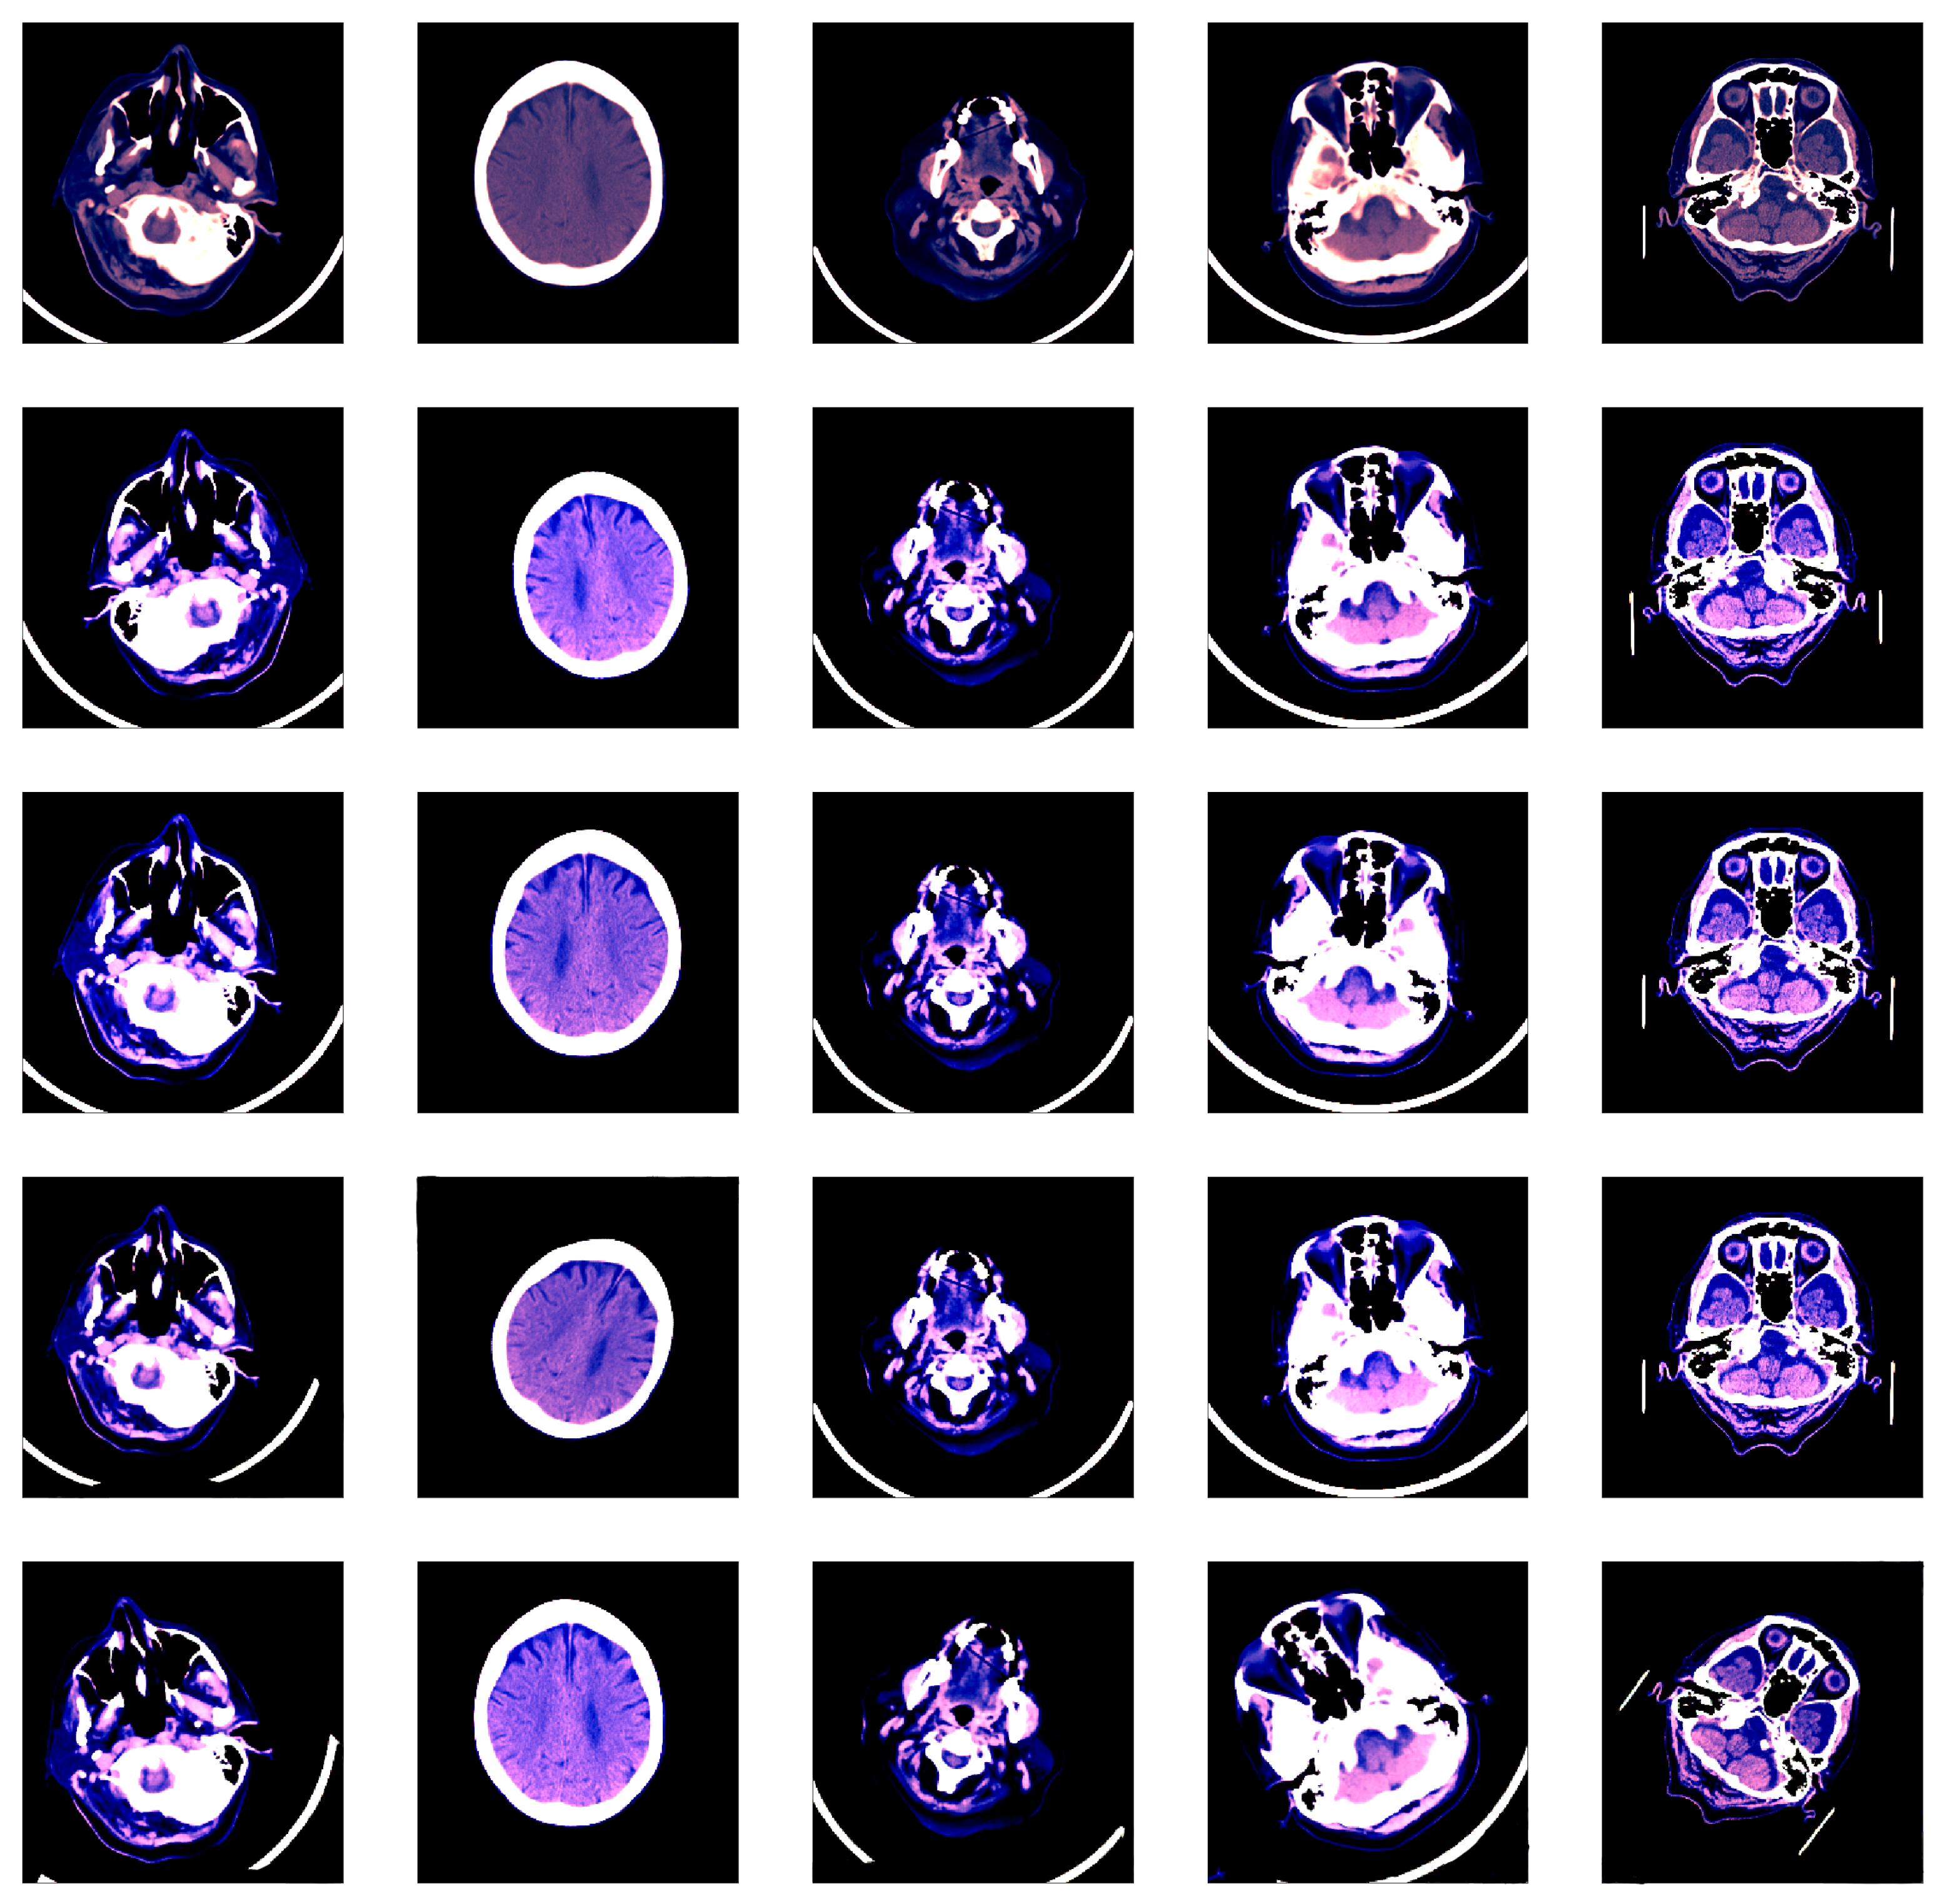

The common format for storing and transmitting medical CT images is DICOM® (Digital Imaging and Communications in Medicine), which contains metadata alongside the pixel data. The RSNA dataset [28] contains 16-bit images, meaning that each image is represented on a scale with 65,536 levels of gray. The value of each pixel represents the density of the tissue measured in Hounsfield units (HU). Since most monitors can only display 256 levels of gray (8-bit images), specialized DICOM software allows radiologists to focus on different intensity windows of HU, which are used to study different tissue types and various pathologies. An intensity window is commonly defined through its center (WC) and its width (WW), specifying a linear conversion from HU to pixels values to be displayed. Radiologists usually look at predefined intensity windows in order to detect a specific pathology. Following the recommendation of trained radiologists for intracranial hemorrhage detection, we consider three HU windows, each focusing on different types of tissue: brain window (, ), subdural window (, ) and soft tissue window (, ). By applying a single HU window on a CT slice, we obtain a grayscale (8-bit) image. The images resulted after applying the three intensity windows recommended by radiologists are combined into a single three-channel image, as shown in Figure 1. While the original CT slices are formed of pixels, we reduce their spatial dimension to cope with the large training set of over 700 thousand slices [28]. The CT slices are reduced to pixels using linear interpolation. Hence, the input of our neural network is . Following the standard preprocessing procedure in training CNN models [50], we normalize all the resulting images by subtracting the mean () and dividing them by the standard deviation () with respect to each channel.

Figure 1.

Preprocessing flow of a single CT slice in DICOM format. Each DICOM file is processed by extracting three different intensity windows (brain window, subdural window, soft tissue window), which are treated as three different channels. The resulting image is what the neural model takes as input. In order to illustrate the final image as an RGB image, we used the following correspondence: brain → red, subdural → blue, soft tissue → green. Best viewed in color.